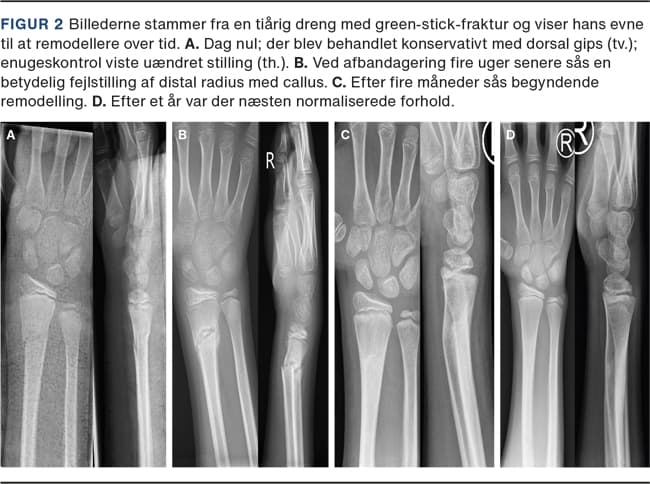

Frakturerne inddeles i epifysiolyser, metafysære og metadiafysære frakturer samt i inkomplette (»torus«-, »buckle«- og »green-stick«-fraktur) og komplette frakturer (Figur 1). Børn har under vækst stor remodelleringsevne, og 75% af længdevæksten og dermed størstedelen af remodelleringen foregår distalt i radius [7]. Evnen til remodellering afhænger af væksthastighed i vækstzonen, restvækst og frakturens afstand fra vækstzonen. Jo tættere frakturen er på vækstzonen, og jo yngre barnet er, des større er remodelleringen. Figur 2 viser et barns evne til at remodellere over tid.